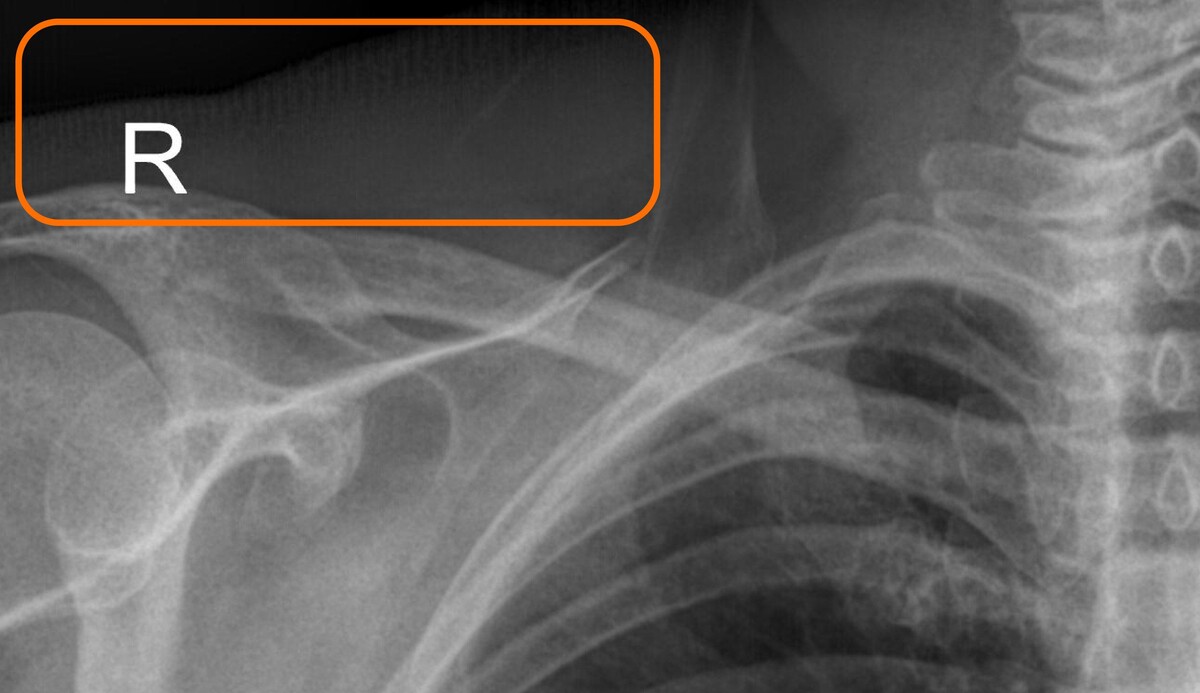

Полосы были тонкие, равномерные, и при беглом взгляде не сразу бросались в глаза. Но при внимательном рассмотрении — особенно на снимках лёгких и ключиц — эти полосы мешали диагностике. Изображение становилось зернистым и «грязным». Врачам приходилось пересматривать кадры, а в некоторых случаях — повторять исследования.

Подобные полосы появлялись на всех снимках, когда излучатель был направлен в стол

На изображении два снимка одного и того же пациента. На первом — активирован неверный режим, и растр не двигается. В отдельных областях видны полосы и заметна общая нечёткость изображения. На втором — всё настроено правильно, растр работает